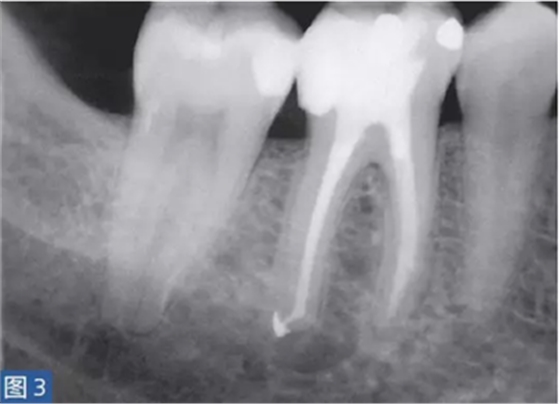

從牙髓炎過渡到根尖周炎(圖2 和3)的發(fā)生速度非常快,牙齒表現(xiàn)可能從正常到對(duì)冷、熱和電刺激的反應(yīng)越來越強(qiáng)。當(dāng)牙髓已經(jīng)完全壞死時(shí),通常會(huì)顯示對(duì)牙髓電活力測(cè)試無反應(yīng)。牙齒可能會(huì)有伸長感,用手指或口鏡柄施加壓力或者振動(dòng)牙齒會(huì)觸發(fā)非常嚴(yán)重的疼痛。放射學(xué)檢查可能存在透射區(qū)及根周膜間隙增寬,通常硬骨板和牙周韌帶沒有病理學(xué)特征。

圖2: 46 牙齒SAP。術(shù)前X 線片,該牙齒在其他醫(yī)生處已行齲齒治療?;颊咴V牙齒有明顯的咬合痛以及強(qiáng)烈的冷熱刺激敏感癥狀。放射學(xué)檢查,近中根根周膜間隙略增寬。

圖3: 46 牙齒SAP。根管治療6個(gè)月后。